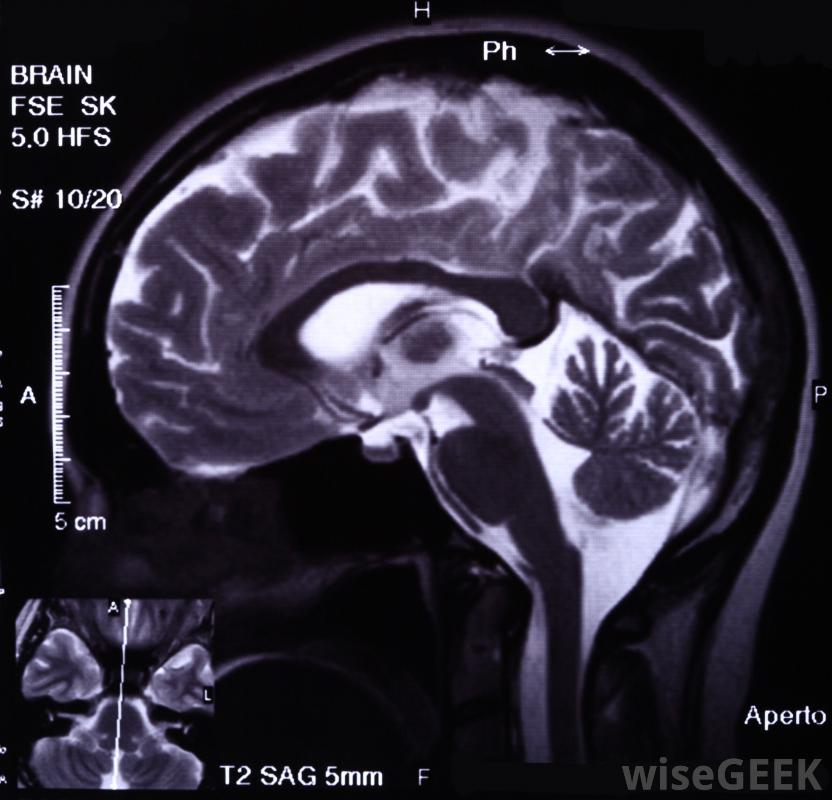

從廣義上講,物理學研究的重點是物理對象、它們的組成物質以及它們在時空中的相互作用和運動。物理學被用來解釋自然界中發生的事件和情況,因此物理學理論是幾個科學學科的重要組成部分,包括天文學,生物學和核研究。物理學在核醫學中的應用涉及到應用物理原理和理論,如放射性衰變、聚變或裂變來產生醫療技術。在最基本的粒子細胞水平上研究物質是核醫學物理學的基石。核物理學的原理是最常用于醫學上的圖像檢測和藥物制作。帶電粒子相互作用被用來創建MRI圖像核醫學是應用物理學的一種形式。物理學在核醫學中的應用是利用物理學理論和分支學科來設計和創造工作對象或執行任務的新方法,它們使用經過嚴格檢驗的科學方法,并試圖應用穩定不變的方法科學定律。例如,量子力學是一個物理學的分支學科,它研究像放射性衰變過程中產生的粒子是如何具有波浪狀特性的,以及這些粒子是如何相互作用和與能量力相互作用的IMG SRC="/img/0730/a-brain-scan.jpg"/>伽瑪相機可用于探測人和039體中的放射性能量。核物理是核技術的基礎,包括核醫學。這一廣闊的領域集中在原子核上,特別是原子核的結構和相互作用。科學家可以操縱這些細胞的內部并產生強大的反應,它通常產生輻射,這是能量在空間中運動的一個基本物理原理。能產生能量的核研究活動包括加速、加熱、轉移、衰變、分裂和聚變。后者在核醫學中尤為突出裂變和聚變是核反應,可以用來為核醫學中的物理學產生能量。前一個事件涉及分裂原子粒子,后者涉及到將原子材料結合在一起。物理學家在稱為核反應堆的裝置中誘導這些反應。在醫學領域,研究反應堆通常用于分析、測試和生產放射性同位素或原子核材料醫學中核物理的一個主要組成部分與診斷成像有關。這些過程也被稱為核素成像,發生在醫生將核素粒子注入人體時。當這些粒子衰變時,它們產生稱為伽馬射線的放射性能量形式像伽瑪照相機這樣的特殊設備可以探測到放射性的差異。這種變化通常能讓人洞察不同身體部位和部位的功能能力。在放射性衰變中,比如在成像實踐中發現的,粒子活動在物理學中被稱為弱相互作用,因為它們不會產生強大的束縛效應。物理學中其他類型的基本相互作用類型包括電磁學和重力。醫生利用電磁學中的帶電粒子相互作用來創建磁共振成像(MRI)物理在核醫學中的另一個應用是當核素材料用于醫療時。例如,當放射性核素材料與某些類型的藥物結合時,這種相互作用的結果是放射性藥物。這些治療方法通常用于特定類型的疾病,如癌癥。直接能源輻射源也可用于癌癥放射治療,即放射射線束直射身體的靶區,希望它們能摧毀有害物質物質。。